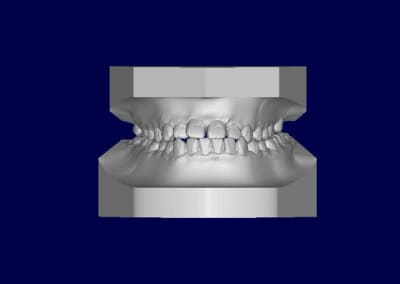

Patient asiatique, 25 ans, consulte car il veut corriger son crossbite bite antérieur localisé aux latérales et son crossbite secteur 2/3. Il aimerait également corriger son apparence générale, son profil notamment.

Classe III squelettique et dentaire.

Pas de shift à la fermeture.

Ci joints photos, ceph, modeles.

il y'a une forte compensation alveolaire maxillaire superieure anterieurement et lateralement,